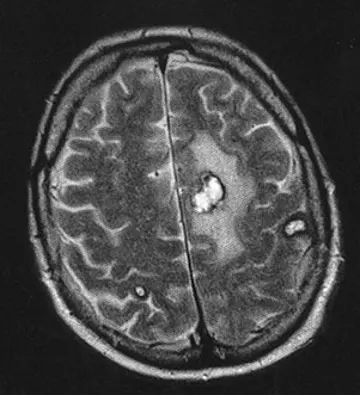

هماتولوژی - صفحه 10